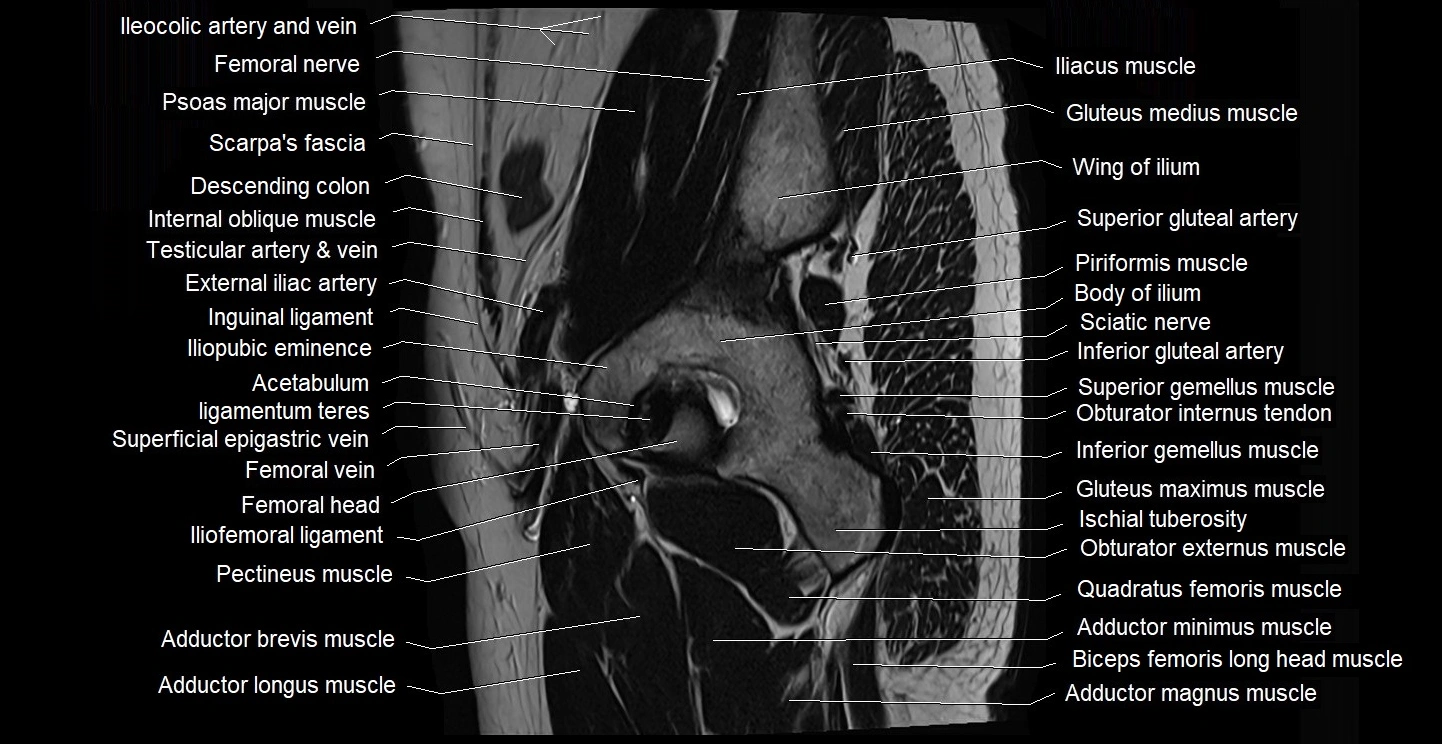

- Acetabulum

- Adductor brevis muscle

- Adductor longus muscle

- Adductor magnus muscle

- Adductor minimus muscle

- Femoral nerve

- Femoral vein

- Gluteus maximus muscle

- Gluteus medius muscle

- Iliofemoral ligament

- Iliopubic eminence

- Inferior gemellus muscle

- Inferior gluteal artery

- Ligamentum teres (ligament of the head of femur)

- Pectineus muscle

- Quadratus femoris muscle

- Superior gemellus muscle

- Superior gluteal artery